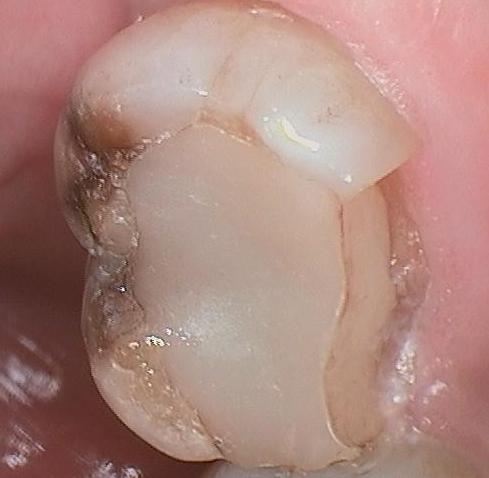

We like to use the white filling material for a few reasons. First we like them because they blend in very nice and look better. Second, we like them because these white fillings act like glue and hold the tooth together. This is known as "bonding." Even if we bond a booth together with a tooth colored filling, overtime this tooth can still breakdown if the filling is large enough. The before photo show a piece of tooth that has broken away from the tooth colored filling. In the same photo, the brown part of the tooth is where ...